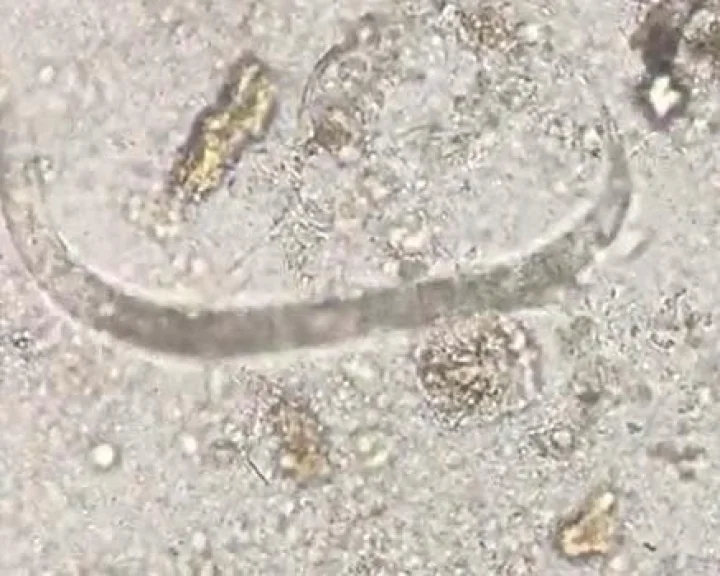

Strongyloidiasis, a chronic parasitic infection of humans